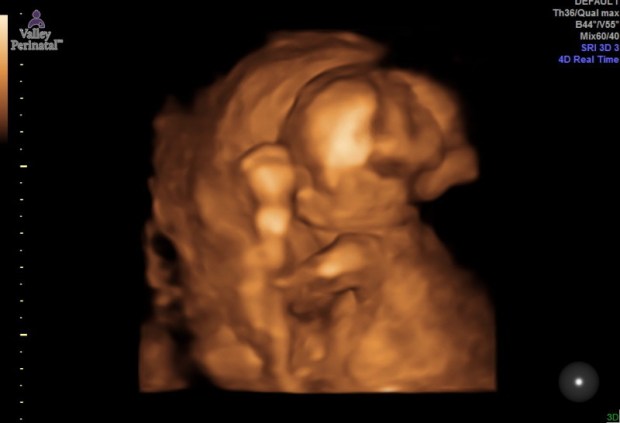

We got to see baby girl during our second trimester ultrasound (18-19 weeks). She was hiding from us behind her arm again during most of the ultrasound but our tech still managed to get some sweet photos. ❤

My favorite photo! Let us peek enough to see that sweet face.